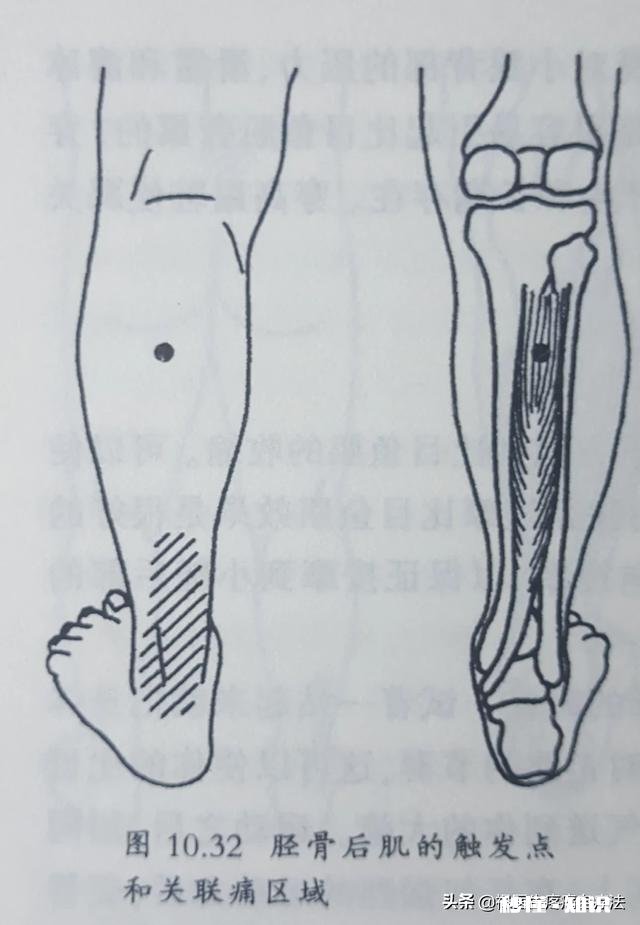

肌肉损伤小腿后面的比目鱼肌和胫骨后肌在我们长期的走路、跑步、爬山后,就有可能出现损伤 。肌肉损伤后出现肌筋膜触发点,胫骨后肌的触发点会引发跟腱的疼痛 。很多被诊断为跟腱炎的患者,其实就是胫骨后肌的损伤 。

文章插图